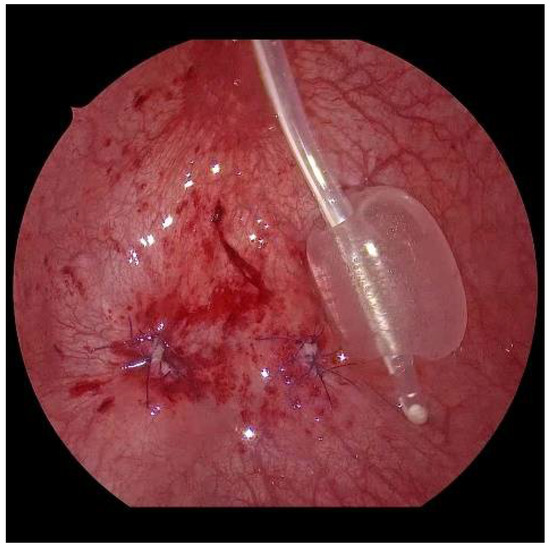

After sparingly shortening and spatulating, the neoostia are created with 5/0 polyglyconate or polyglactin sutures (Figure 7). Depending on the age of the patient, a submucosal ureteral course of 3 to 5 cm in length can thus be achieved. If the finding is unilateral, the original mucosa incision must be closed (Figure 8). Only in exceptional cases, e.g., renal insufficiency, are the ureters splinted for 6 days by percutaneously inserted splints. Finally, the bladder is drained through a balloon catheter for at least 1 to 2 days. After the trocars have been removed, the trocar incisions are only adapted cutaneously, using skin patch strips. The patients are discharged home with problem-free, spontaneous micturition, safe well-being, and regular ultrasound findings.

Figure 8. Aspect at the end, with closed mucosal defect on the right and the neoostium on the left.